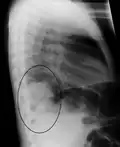

A black and white X-ray picture showing a triangle white area on the left side. A circle highlights the area.

A chest X-ray showing a very prominent wedge-shape bacterial pneumonia in the right lung

The discovery of x-rays made it possible to determine the anatomic type of pneumonia without direct examination of the lungs at autopsy and led to the development of a radiological classification. Early investigators distinguished between typical lobar pneumonia and atypical (e.g. Chlamydophila) or viral pneumonia using the location, distribution, and appearance of the opacities they saw on chest x-rays. Certain x-ray findings can be used to help predict the course of illness, although it is not possible to clearly determine the microbiologic cause of a pneumonia with x-rays alone.